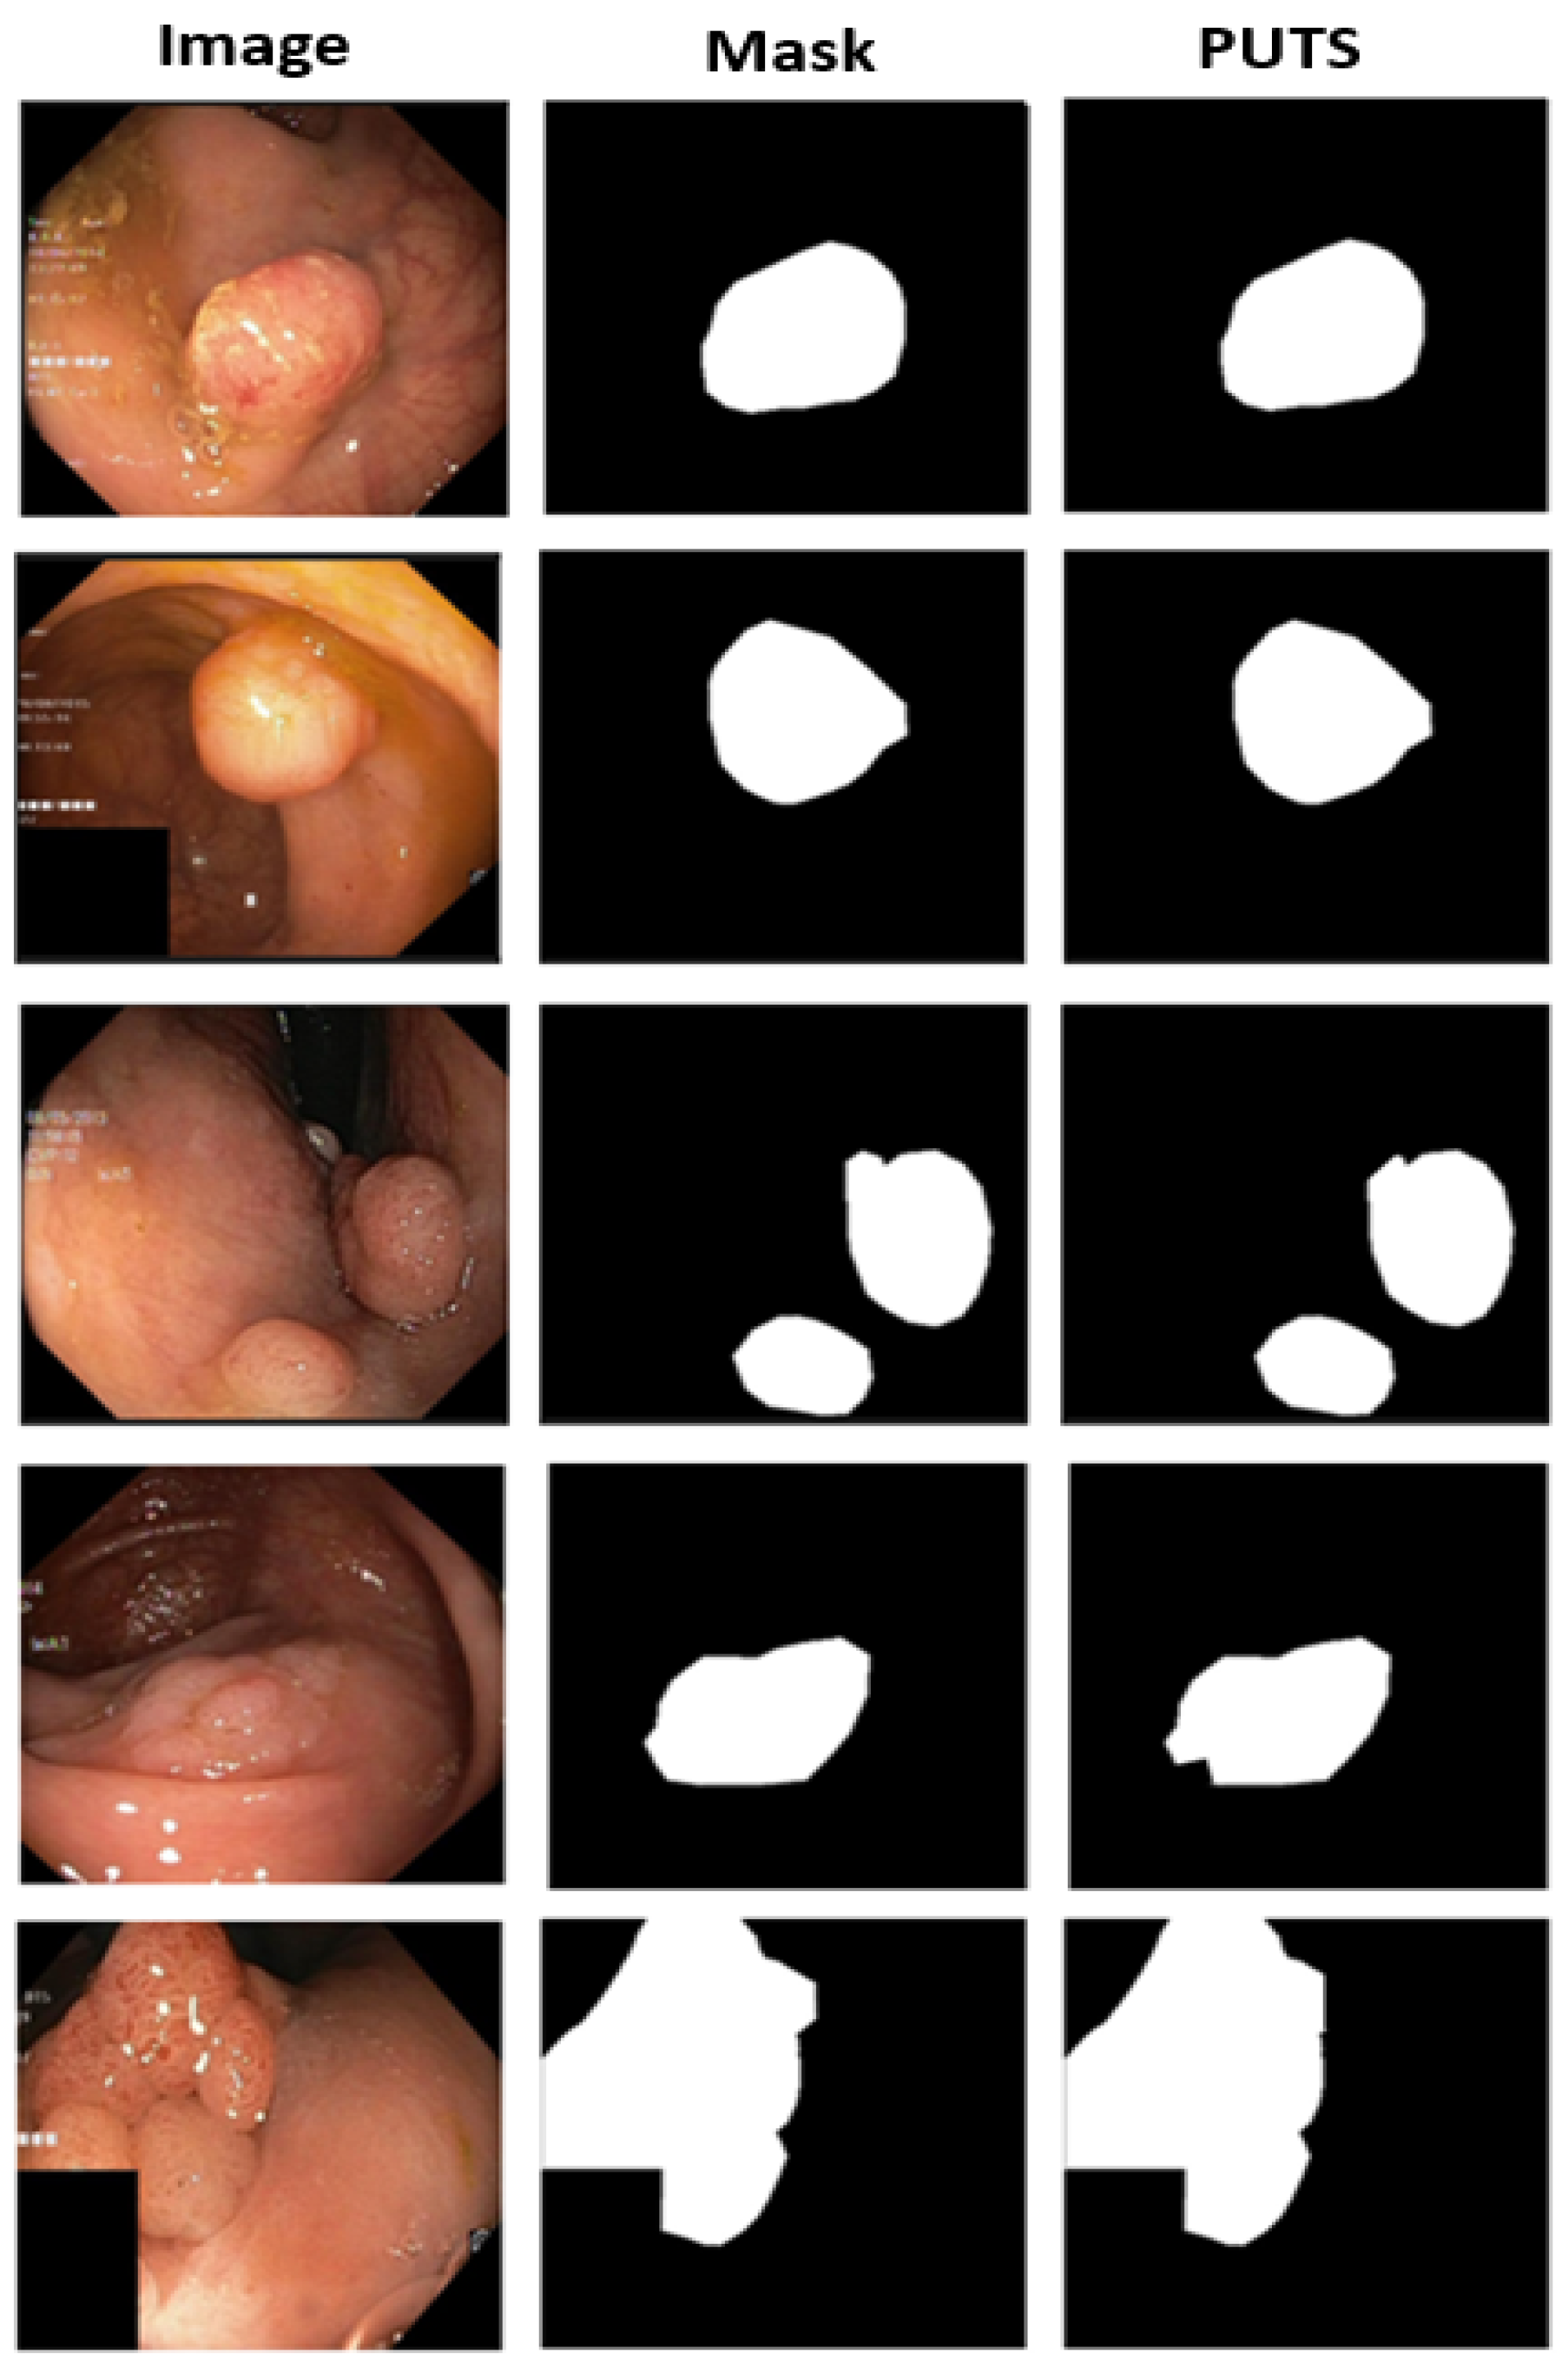

- PUTS: A novel Swin-Unet transformer-based polyp segmentation model;

3.2. PUTS: Vision Transformer-Based Polyp Segmentation

3.2.1. Motivation

3.2.2. PUTS Architecture

4.2. Polyp Segmentation Performance Results